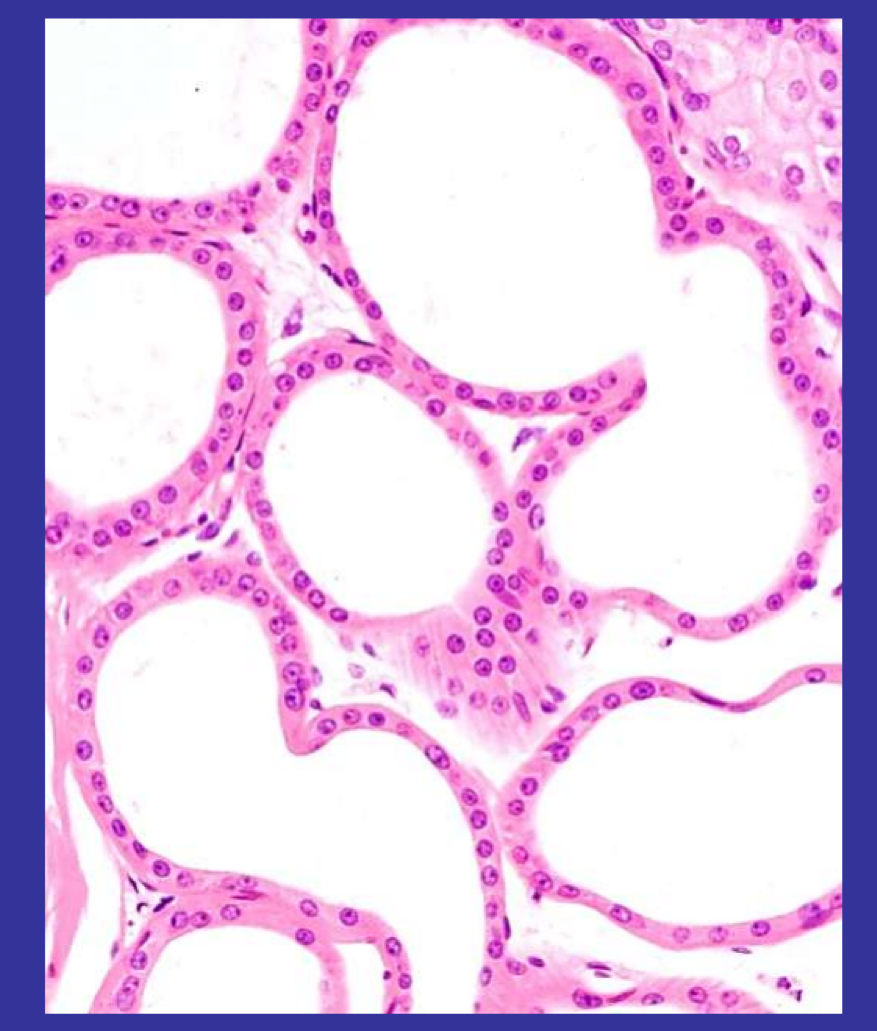

What type of cells line the colloid and where is it found?

Simple cuboidal epithelium bounding thyroid gland follicles (follicular cells)

The epithelial cells synthesise thyroxine, store it in colloid, and transport it to the bloodstream

Arrows show fine blood capillaries